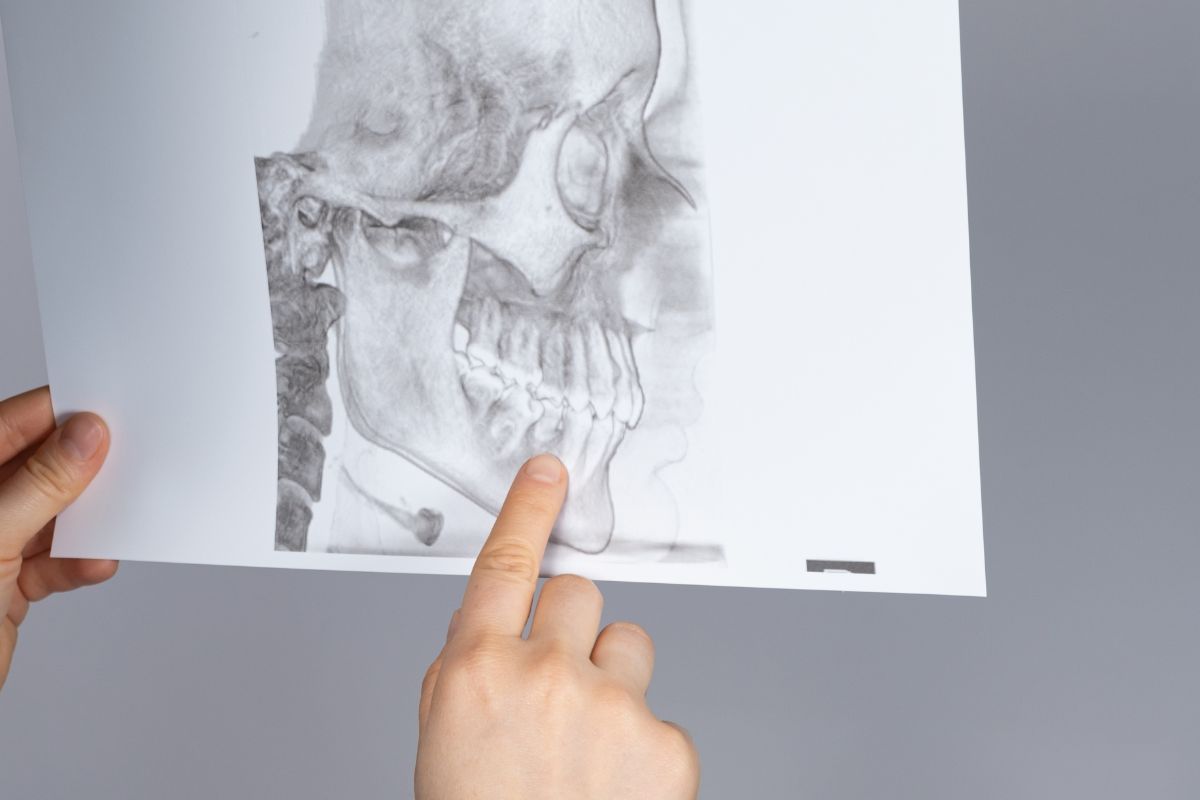

Diagnóstico de la ATM:

Un diagnóstico preciso es fundamental para el desarrollo de un plan de tratamiento efectivo para los trastornos de la ATM. Esto puede implicar una evaluación clínica completa, pruebas de imagen y, en algunos casos, pruebas de laboratorio.

La evaluación clínica incluirá un examen detallado de la mandíbula, la cabeza, el cuello y la cara, evaluando la amplitud de movimiento, la presencia de dolor o sensibilidad, y los sonidos asociados con el movimiento de la mandíbula.